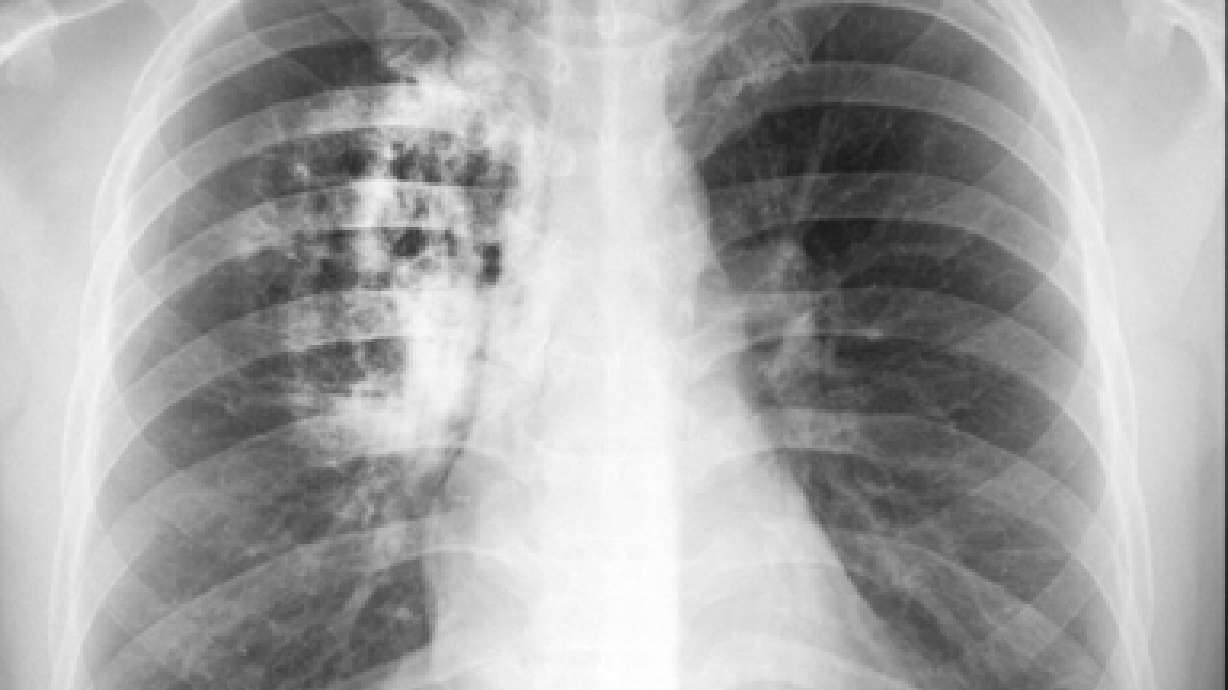

Las autoridades de sanidad de Estados Unidos reportaron el jueves un descenso en la tasa de nuevos casos de cáncer de pulmón.

Los Centros para el Control y la Prevención de Enfermedades informaron que las tasas de incidencia de cáncer de pulmón se redujeron casi 3% anual entre hombres y 1% entre mujeres de 2005 a 2009.

El mayor descenso fue en el grupo de 35 a 44 años de edad, donde las tasas cayeron 6% por año para ambos sexos.

Las autoridades atribuyen la baja a las iniciativas para control del tabaco. Las tasas de tabaquismo han disminuido de manera constante desde hace años, y las cifras más recientes indican que un 18% de los adultos fuman.

El cáncer de pulmón sigue siendo el asesino más letal en el mundo entero. Esta semana se cumplieron 50 años del primer reporte del director de salud pública de Estados Unidos que vinculó el tabaquismo con el cáncer de pulmón.